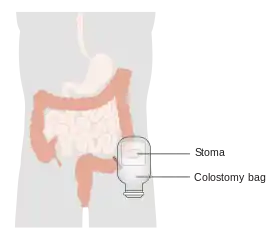

Diagram showing a colostomy | |

A colostomy is an opening (stoma) in the large intestine (colon), or the surgical procedure that creates one. The opening is formed by drawing the healthy end of the colon through an incision in the anterior abdominal wall and suturing it into place. This opening, often in conjunction with an attached ostomy system, provides an alternative channel for feces to leave the body. Thus if the natural anus is unavailable for that function (for example, in cases where it has been removed in the fight against colorectal cancer or ulcerative colitis), an artificial anus takes over. It may be reversible or irreversible, depending on the circumstances.

Pouches and the stick-on appliances to which they attach must be changed regularly. Sometimes an odor neutralizer and lubricant is squirted into a new pouch before it is attached. Two types of pouches are available: one disposable and one drainable. Most pouches are opaque and filter out air through a charcoal filter. The recommended practice is to empty such pouches when one-third full.[5] Appliances, in contrast with pouches, are usually replaced every three to seven days except in cases where their seals have broken contact with the skin, when they should be replaced immediately.[5]

People with colostomies must wear an ostomy pouching system to collect intestinal waste. Ordinarily, the pouch must be emptied or changed a couple of times a day depending on the frequency of activity; in general the further from the anus (i.e., the further 'up' the intestinal tract) the ostomy is located the greater the output and more frequent the need to empty or change the pouch.[7]